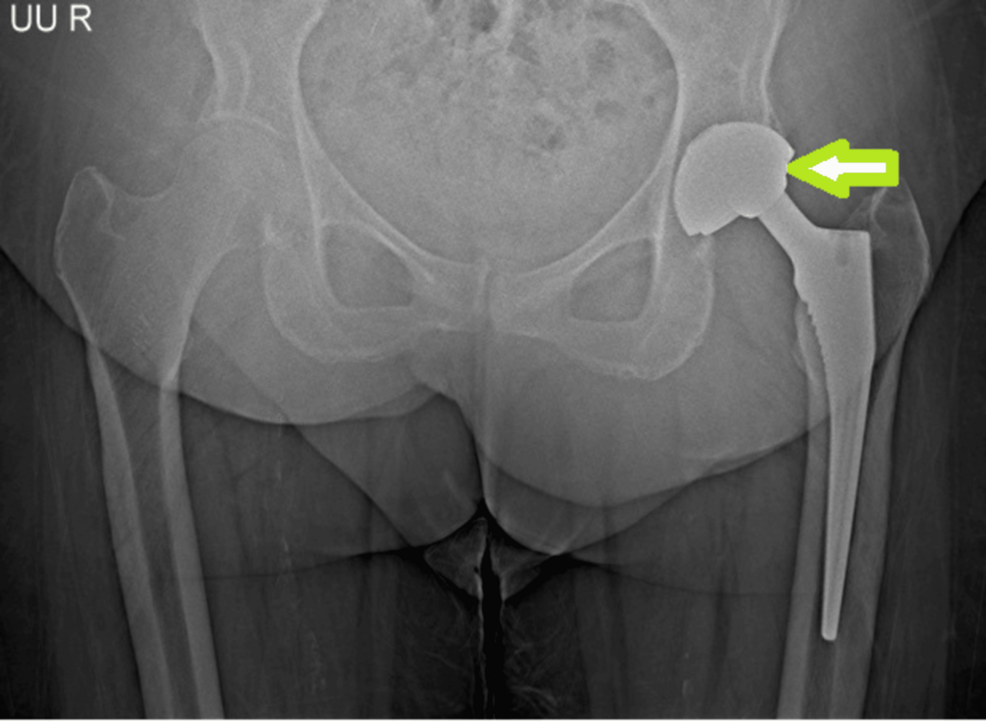

A pesar de que los implantes de movilidad dual ofrecen un excelente rango de movimiento y bajas tasas de dislocación, existe una complicación específica denominada dislocación intraprostética (DIP). Esta ocurre cuando el revestimiento de polietileno se disloca, provocando que la cabeza protésica articule directamente con la copa metálica.

Este modo de falla es exclusivo de los implantes de movilidad dual y ha sido documentado en reportes de casos, como el publicado recientemente por Cureus.